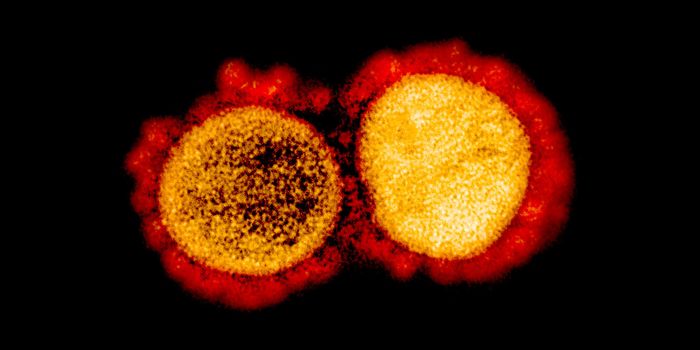

MAR 14, 2022ImmunologyThough it may happen at different rates for different microbes, mutations happen, and SARS-CoV-2, the virus that causes ...

NOV 26, 2021MicrobiologyOn Thursday, November 2021, South African health officials announced that they had identified a new variant of the pande ...

MAY 04, 2021ImmunologyThere are currently five variants of concern in the U.S., genetically distinct forms of the COVID-causing coronavirus th ...